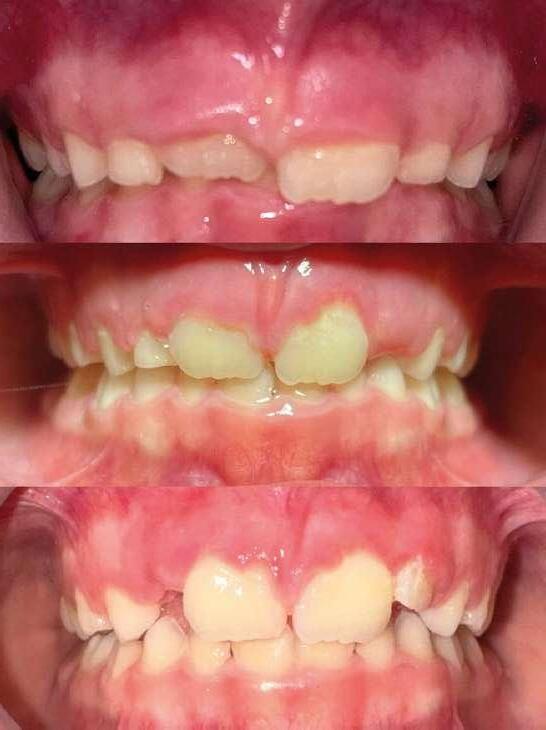

Imágenes 1 y 2. Caso de paciente de 8 años, sexo masculino. En tratamiento se pueden ver los cambios estructurales y oclusales al modificar las funciones de respiración y posición lingual con sistema miofuncional, en 5 meses.

1 2